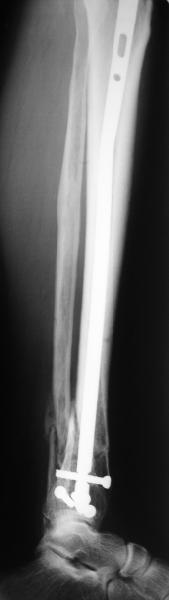

A typical case is attached, also an image with intra-op reduction obtained by a small wire distractor, in the moment of insertion a Poller wire in AP direction. Fixation by a SIGN nail. Despite the fibula was not fixed healing was obtained with the unchanged alignment.

Very interesting application, but is the final position in a little distal varus with some fibula

distraction? Would that have been eliminated by fibula plating?

TDVC> Very interesting application, but is the final position in a

TDVC> little distal varus with some fibula distraction?

At least both the ankle mortise and tibial alignment look acceptable, don't they?

TDVC> Would that have been eliminated by fibula plating?

I am just trying to illustrate that prevention of 1)tibial valgus and 2)loss of reduction can be provided without fibular plating. Small changes of conventional nailing techniques allow to maintain reduction of the tibia reliably without adjunctive fibular stabilization.